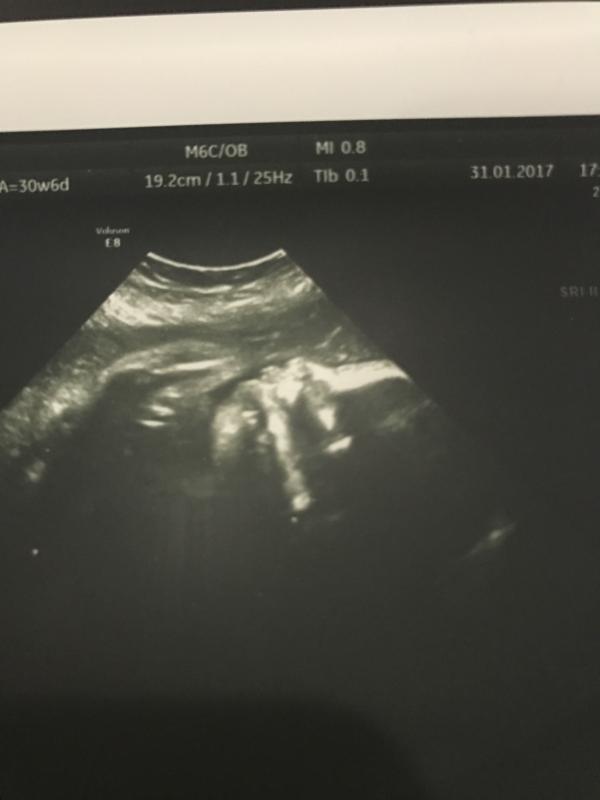

Девочки, только была на УЗИ у Полтева М.Ю. Подтвердил он преждевременное старение плаценты и поставил маловодие😔понимаю, что без больницы не обойтись😰😖не хочууууу....к врачу 2 февраля идти! Ну а в целом с доченькой все прекрасно, 1800кг, обвитая нет, головное предлежание!